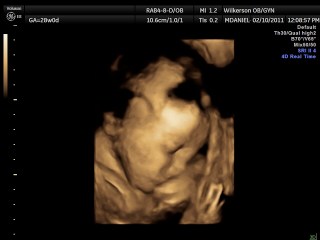

We had our 4-D ultrasound today. James would not cooperate at all but Jackson did. He was so precious he kept his hand over his face though. It was so neat. They are definitely cramped in there. We go back Monday and hopefully James will work with us. Here our a few pictures we have more but they are video rather than pictures.

Here is sweet Jackson: